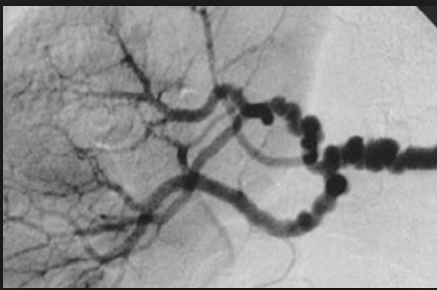

What is this?

Lesions of PN may vary in stages. Early lesions consist of transmural inflammation with fibrinoid necrosis that eventually heal with fibrosis, producing a ‘string of pearl’s appearance’ on imaging